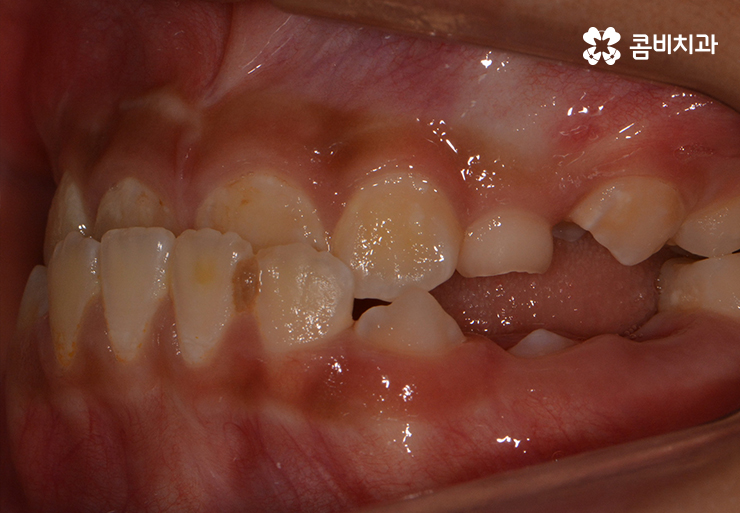

많지만 위 사례 이미지와 같이 교합이 맞물리지 않는 경우에는

심미적인 부분을 떠나서 식사를 할 때마다 불편함을 느끼게 된다거나

발음이 새고 턱관절에 무리가 올수 있는 등 건강 상의 문제가 발생할 수 있습니다.

(위턱과 아래턱의 성장 불균형으로 인해 주걱턱이 발생한 사례)

위와 같은 사례를 부정교합 중에서도 반대교합이라고 하는데

성장기에 턱이 성장을 할 때 아래턱이 과도하게 발달을 하거나

반대로 위턱의 성장이 부족한 경우에 이와 같은 주걱턱 증상이 발생할 수 있습니다.